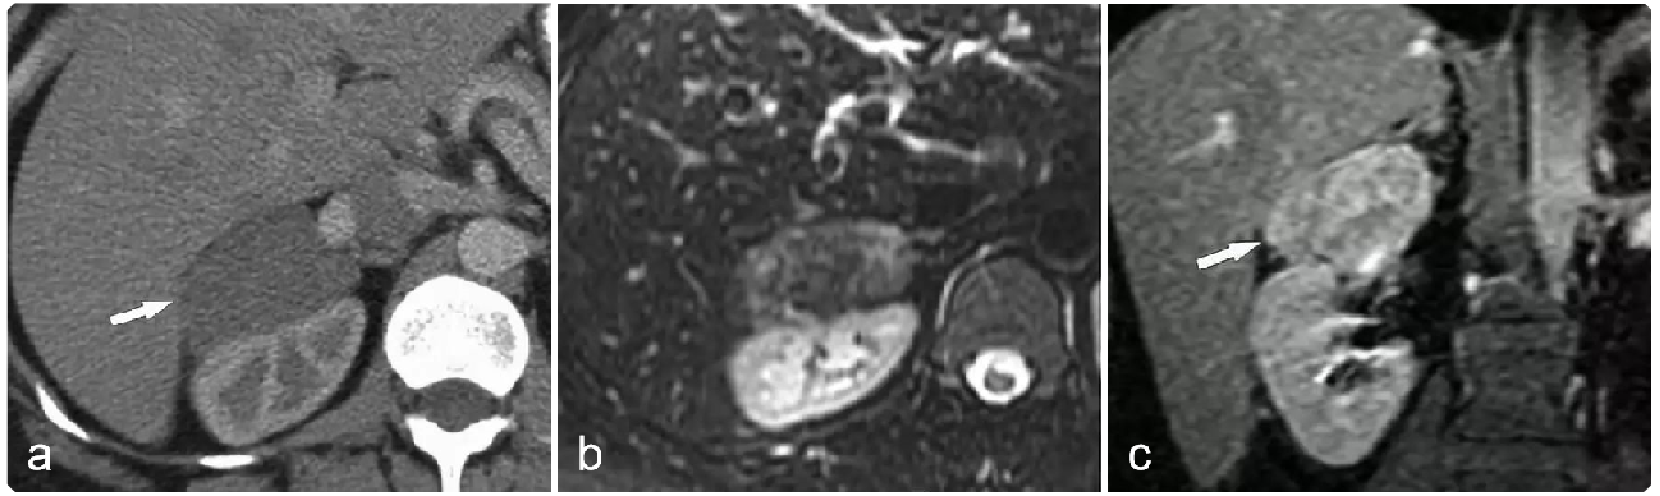

309da72b651fad69b53c1ea5f4ca297c.png 病例 24:(腹膜后)神经鞘瘤囊变  41岁女性,偶然发现腹部肿块(a) CT增强显示低密度肿块,内见线样钙化(箭)。(b) T2WI-FS显示肿块呈不均匀高信号,内见囊变区形成(*)。(c) 大体病理显示肿瘤界限清楚,具有棕黄色实性和囊性切面(箭),其中60%为白色纤维组织,40%为黄色脂肪组织。中央为出血性囊性成分(*)。(d) 镜下显示中央囊肿(*)及周围更小的囊肿(箭)(HE×40)。(e) 高倍镜显示由栅栏样细胞(箭头)组成的Verocay小体,这些细胞被低细胞透明化区域(*)隔开(HE×200)。